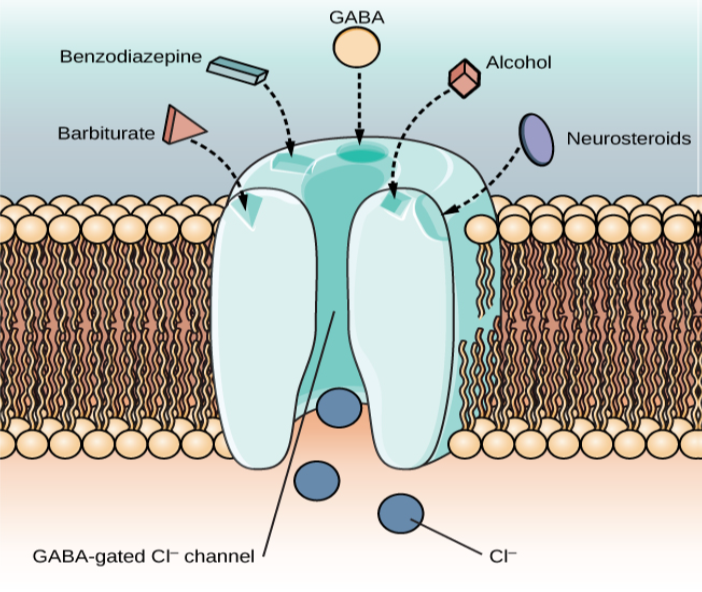

Ethanol, which we commonly refer to as alcohol, is in a class of psychoactive drugs known as depressants (Figure 4.15). A depressant is a drug that tends to suppress central nervous system activity. Other depressants include barbiturates and benzodiazepines. These drugs share in common their ability to serve as agonists of the gamma-Aminobutyric acid (GABA) neurotransmitter system. Because GABA has a quieting effect on the brain, GABA agonists also have a quieting effect; these types of drugs are often prescribed to treat both anxiety and insomnia.

With repeated use of many central nervous system depressants, such as alcohol, a person becomes physically dependent upon the substance and will exhibit signs of both tolerance and withdrawal. Psychological dependence on these drugs is also possible. Therefore, the abuse potential of central nervous system depressants is relatively high.